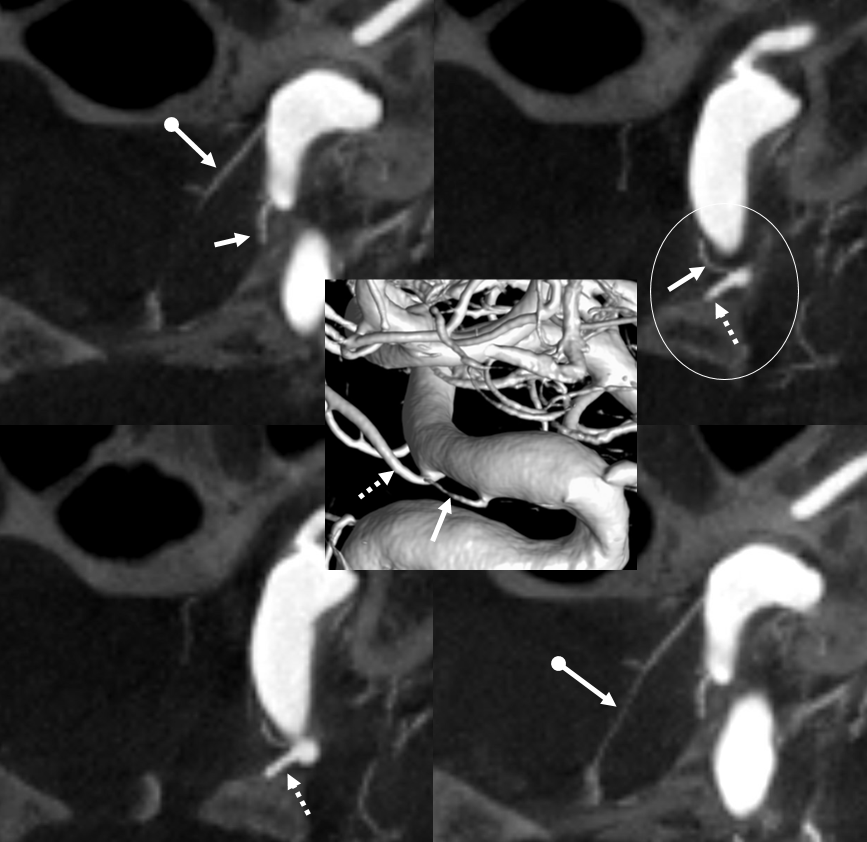

Optic Nerve Supply

What supplies the bulk of optic nerve? Central Retinal artery is for the distal portion of nerve and retina. What about the rest — intracranial, intracanalicular, proximal intraconal segments? The answer is not clear (let me know if you do), but i believe the bulk of it comes from the superior hypophyseals. It is probably in balance with the recurrent branch of the central retinal artery. Below is an example of an especially prominent proximal-most superior hypophyseal (arrows) supplying the pituitary stalks and optic nerve in the canalicular and intracranial locations. Note how well one can see the branch in coronal view (bottom left image). In this case there are two large superior hypophyseals — the more distal one (dashed arrows) supplies predominantly the pituitary stalk. The inferior hypophyseal artery is marked by arrowhead. Lower right image is coronal.

Movie is the best way

Here too superior hypophyseal (arrow) supply of the intracranial optic nerve (oval) and possibly chiasm is shown definitively (lower right image is coronal)

No annotations